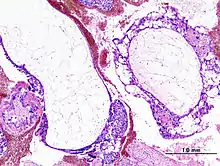

| Histopathologic image of hydatidiform mole (complete type). H&E stain. | |

Based on morphology, hydatidiform moles can be divided into two types: in complete moles, all the chorionic villi are vesicular, and no sign of embryonic or fetal development is present. In partial moles some villi are vesicular, whereas others appear more normal, and embryonic/fetal development may be seen but the fetus is always malformed and is never viable.